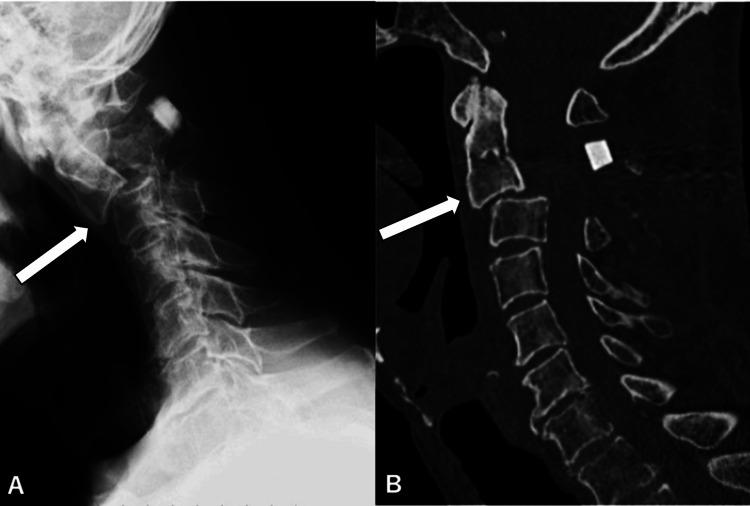

Traumatic herniations of the upper cervical spine are rare, with a higher likelihood of occurrence in older individuals. Their associated neurological symptoms can vary widely, often leading to delays in clinical diagnosis. We report the case of an 86-year-old man who developed neurological symptoms after a fall. Initially, intracranial pathology was suspected, and a head magnetic resonance imaging (MRI) revealed small chronic subdural hematomas, which were managed conservatively. However, as his paralysis progressed over the following days, a repeat brain CT showed no significant changes. Suspecting cervical spine involvement, further imaging identified a C2/3 disc herniation. The patient underwent emergency cervical laminoplasty, but postoperative subluxation required additional surgery, including C1-3 posterior fusion and C2/3 anterior fusion. Post-surgery, the patient exhibited improvement in paralysis affecting both the upper and lower extremities and a reduction in sensory deficits. Early diagnosis and treatment are crucial to improve neuropathic outcomes. A thorough understanding of the symptoms and characteristics of neurological damage to the upper cervical spine can significantly contribute to favorable results. Clinicians should be well-acquainted with this pathological condition.